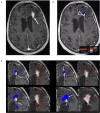

In the follow-up treatment of high-grade gliomas (HGGs), differentiating true tumor progression from treatment-related effects, such as pseudoprogression and radiation necrosis, presents an ongoing clinical challenge. Conventional MRI with and without intravenous contrast serves as the clinical benchmark for the posttreatment surveillance imaging of HGG. However, many advanced imaging techniques have shown promise in helping better delineate the findings in indeterminate scenarios, as posttreatment effects can often mimic true tumor progression on conventional imaging. These challenges are further confounded by the histologic admixture that can commonly occur between tumor growth and treatment-related effects within the posttreatment bed. This review discusses the current practices in the surveillance imaging of HGG and the role of advanced imaging techniques, including perfusion MRI and metabolic MRI.